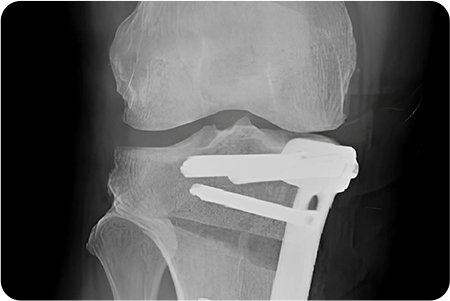

2

무게 중심이 외측으로

쏠려 있는 X다리 수술

교정 각도를 정밀하게 설계해 수술 계획을 세웁니다.

대퇴골을 절골하여 원하는 각도로 닫거나 벌려

무게 중심이 무릎 안쪽으로 옮겨지도록 교정

합니다.